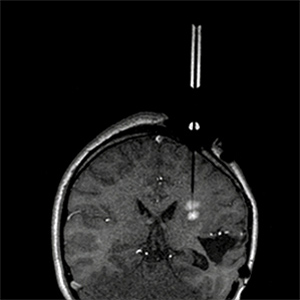

Los neurocirujanos pueden usar esta tecnología de toma de imágenes durante cirugías en las que hay que colocar pequeños objetos -agujas de biopsia, implantes o tubos para administrar fármacos- en lugares concretos del cerebro. El sistema proporciona imágenes por resonancia magnética (RM) en vivo que permiten a los cirujanos seguir sus progresos durante la operación.

El sistema de MRI Interventions funciona con escáneres de RM convencionales. Se fija al cráneo una plataforma para guiar a las herramientas quirúrgicas o a los implantes dentro del cerebro, y proporciona un sistema de cuadrícula para decidir la trayectoria. Uno de los materiales con los que está fabricada la plataforma hace que el dispositivo resulte visible al escáner. Software exclusivo de MRI Interventions muestra a los cirujanos dónde están sus herramientas respecto al cerebro del paciente. Esos datos se muestran en una pantalla compatible con la RM para que los cirujanos tengan una visión de lo que sucede dentro del cráneo del paciente, y que no interfiere con el procedimiento de toma de imágenes, un problema asociado con la mayoría de los equipos electrónicos.

"Si el cerebro se ha movido, podrás ver esa variación en la trayectoria", sostiene Gross, que usa el sistema junto con láseres médicos para destruir las pequeñas regiones de tejido cerebral que producen ataques en pacientes epilépticos.